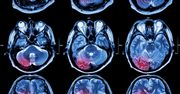

Guz mózgu - objawy, diagnostyka, rodzaje, leczenie

Glejak mózgu - objawy, leczenie, rokowania

Glejak - objawy, przyczyny, diagnostyka, rokowania i leczenie

Rak mózgu – objawy, leczenie